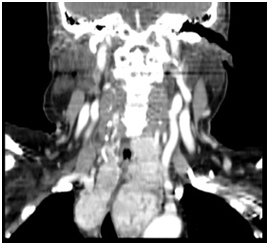

Figure 4 Goiter extending under aortic arch (coronal view).